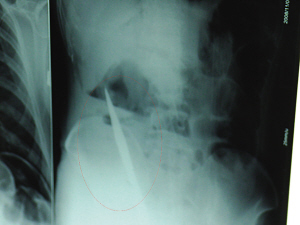

X光片上,尖刀清晰可見。

從男子體內(nèi)取出的尖刀足足有19厘米長。

6日上午,記者在徐州礦務(wù)集團總醫(yī)院重癥監(jiān)護室見到了這名男子,目前他雖然已經(jīng)恢復(fù)了意識,但還不能開口說話,需要呼吸機輔助呼吸。據(jù)醫(yī)生介紹,4日中午12時左右,這名男子因服毒輕生被緊急送到醫(yī)院進行搶救,之前,這名男子已經(jīng)在當(dāng)?shù)剜l(xiāng)鎮(zhèn)醫(yī)院進行了近20小時的治療,但效果不佳!安∪吮晦D(zhuǎn)院到礦總院時已神志不清,血壓極低,處于休克狀態(tài)!本茸o人員給男子洗胃、初步處理以后,發(fā)現(xiàn)男子呼吸急促,于是趕緊給他拍片檢查。結(jié)果讓所有的醫(yī)生大吃一驚,竟有一把尖狀異物橫在該男子腹腔內(nèi)!當(dāng)天下午5時30分,輕生男子被推上了手術(shù)臺。經(jīng)過40多分鐘的手術(shù),該男子腹腔被打開,手術(shù)醫(yī)生發(fā)現(xiàn),男子體內(nèi)的金屬狀異物竟然是一把長19厘米的尖刀!